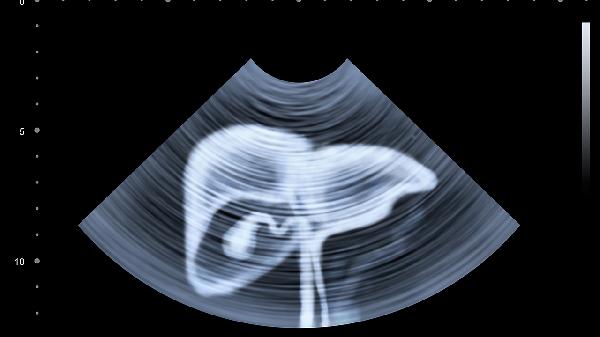

建议每日饮水量达到体重公斤×30毫升,分次小口饮用避免一次性大量摄入加重肾脏负担。可交替饮用蒲公英根茶、菊花茶等具有利胆作用的草本茶饮,但肝硬化患者需控制饮水量。长期接触印刷、化工等行业者应做好职业防护,每年进行肝脏超声和弹性检测。烹饪时开启抽油烟机,减少油烟中的多环芳烃吸入。保持乐观情绪,研究显示持续6个月的抑郁状态会使肝脏代谢效率下降15%。